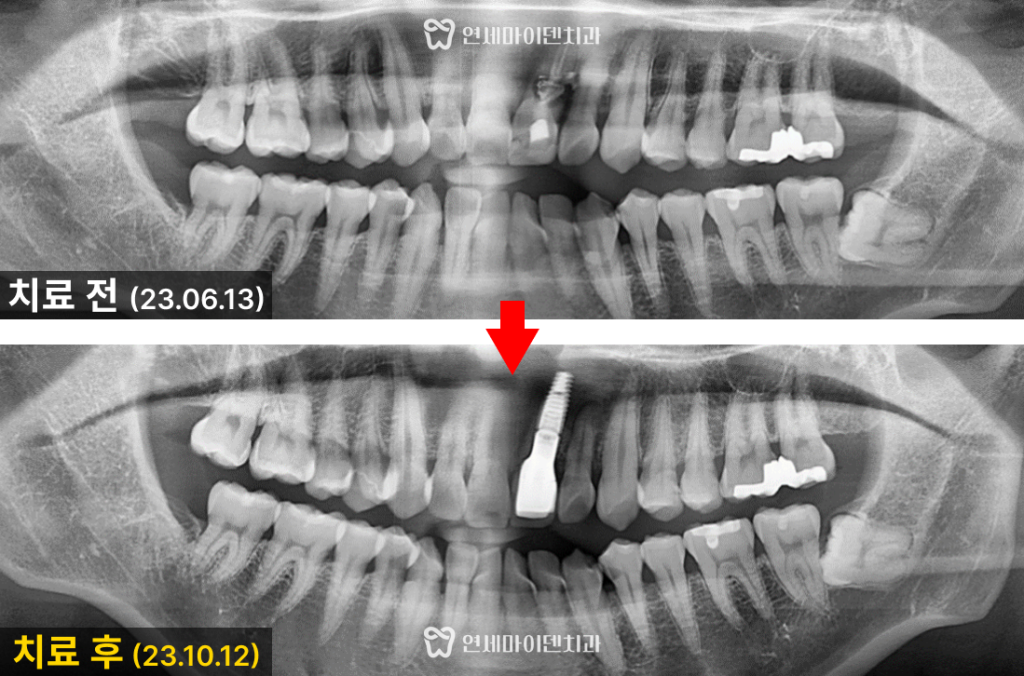

환자분의 치아 방사선 사진을 살펴보면

뿌리쪽 뼈가 까맣게 녹았고, 옆쪽으로 빠져나간 약제도 보입니다.

뼈도 이미 많이 녹았고 염증도 심해서

재신경치료만으로는 회복이 어려울 것으로 보였습니다.

환자분과 충분한 상의 끝에 앞니를 발치한 후

앞니 임플란트를 식립하기로 했습니다.

특히, 치근 내흡수로 뼈가 많이 녹았기 때문에

임플란트 식립과 동시에 뼈 이식도 충분히 해준 뒤 치료를 마무리했습니다.